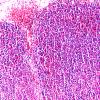

NEOPLASMS (HEMATOLYMPHOID)

Granulocytic Sarcoma